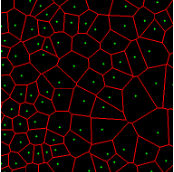

Point annotation can be viewed as the most efficient manner for annotation, gaining increasing attention in cell/nuclei segmentation. Existing methods [23, 24, 25, 26] mainly encode the point annotation into coarse pixel-level labels, such as point distance maps [23], Voronoi labels [24], cluster labels [25], and pseudo edge maps [26]. As shown in Fig. 1, these methods typically inject the shape and texture prior knowledge of nuclei into coarse pixel-level label. For example, the points are assumed to be around the center and the nuclei shapes are nearly convex. Despite drastically reducing the annotation cost and alleviating the data-imbalance problem of point annotation, these methods still suffer from incomplete coarse labels and inaccurate boundary information, as illustrated in Fig. 1. Various methods have been proposed to eliminate the distraction induced by the coarse labels, which can be categorized into two classes: 1) multi-stage optimization to refine the segmentation in a bootstrapping way [23, 27, 24]; 2) adding additional constraints based on the local contrast between nuclei and their surrounding cytoplasm [25, 26]. However, the additional constraints could introduce inaccurate supervision, and a multi-stage learning strategy may suffer from error accumulation (i.e., the global optimum cannot be guaranteed).

In practice, directly using point annotation for the nuclei segmentation could suffer from the data-imbalance problem due to insufficient supervision information. To alleviate this issue, we adopt the Voronoi diagram [24] and the -means clustering method [25] to generate Voronoi label and cluster label, respectively. Specifically, for Voronoi labels, as shown in Fig. 1, the image is divided into convex polygons based on the point annotations with the assumptions that the point labels are at the nuclei centers and nuclear shapes are convex (even though these assumptions are not necessarily valid). For cluster labels, as shown in Fig. 1, we utilize the -means to obtain more supervision information of nuclei boundary and shape as follows. First, we calculate the distance maps from the point labels by performing distance transform between each pair of points. Second, the distance maps are combined with the original H&E stained images to conduct the -means clustering to divide all pixels into clusters: nuclei, background, and ignored area. The clusters that have maximum and minimum overlap with the point annotations are labeled as nuclei and background, respectively. The remaining one is the ignored class. The introduction of an ignored area allows pixels that cannot be easily determined as nuclei or background with certainty not be forced into either class, ensuring that the clustering can assign correct pixel labels as much as possible [27]. Third, several morphological operations are adopted to refine the cluster label, including connected domain labeling, scattered region removing, morphological opening operation, and binary hole filling.

As shown in Fig. 1, although part of the color information is lost in the obtained H-component image, the color contrast between the nuclear and non-nuclear regions is enhanced.

where and denote the Voronoi label and cluster label of nuclei at the -th pixel, respectively; denotes the prediction of the segmentation network with H-component as input; and (i.e., or ) is the set of non-ignored pixels. As illustrated in Fig. 1, the Voronoi label is used to supervise the network to separate overlapping nuclei, while the cluster label could provide coarse shape and boundary information for nuclei segmentation. In the following, we elaborate the co-training strategy to further provide supervision to the ignored area of the coarse cluster labels, denoted with the blue color in Fig. 1.